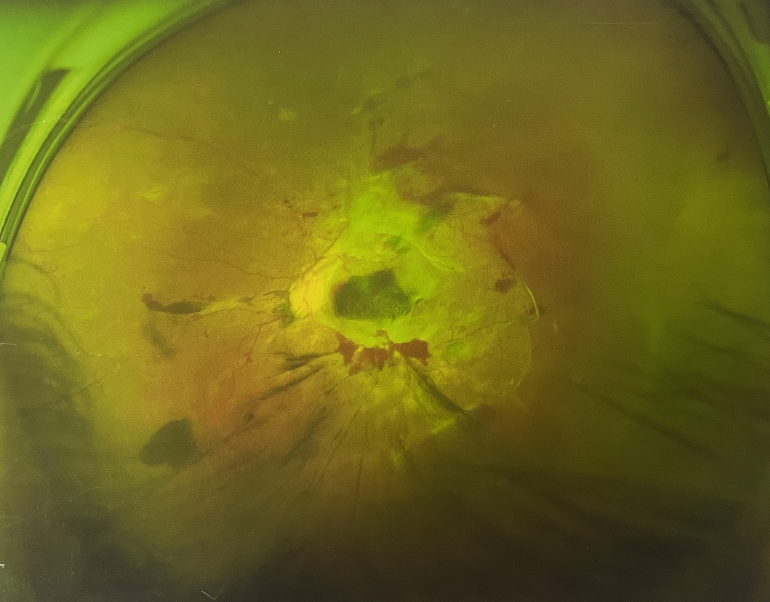

由于王女士的左眼沒有聽從醫(yī)生盡快做手術(shù)的建議,一直耽誤,從4月前的0.4視力逐漸下降到僅剩眼前手動,導(dǎo)致左眼發(fā)展到糖尿病視網(wǎng)膜病變VI期(屬于6期糖網(wǎng)中的晚期),已經(jīng)產(chǎn)生大量新生血管+纖維增值+廣泛牽拉性視網(wǎng)膜脫離,由于耽誤了病情,且病情發(fā)展異常迅速,導(dǎo)致目前左眼連保住眼球都很困難。

“而如果4月余前,左眼及時手術(shù)(當時左眼病情比右眼輕,增殖膜還未累及黃斑),左眼將恢復(fù)的比右眼還好,甚至可以恢復(fù)到0.8或1.0,而現(xiàn)在連保住眼球的機會都很渺茫”,張小虎醫(yī)生表示實在可惜。

左眼發(fā)展到糖尿病視網(wǎng)膜病變VI期